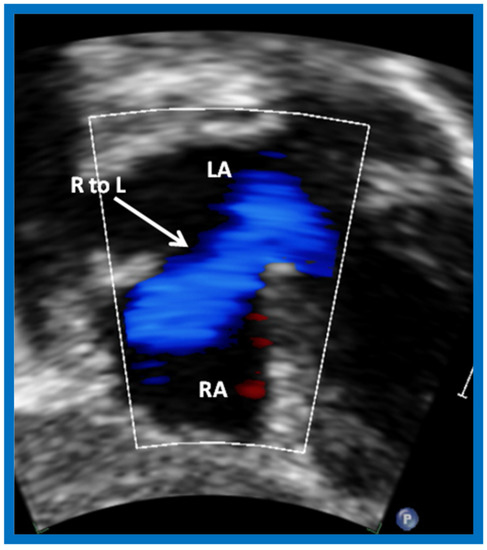

Following the demonstration of the atretic tricuspid valve, the sizes of the cardiac chambers were evaluated both by M-mode (Z scores) and 2D echocardiography; enlarged RA, LA and LV, and a small RV, were seen (Figure 14, Figure 15, Figure 16 and Figure 17). Pulsed (not shown) and color Doppler (Figure 19) studies were helpful in illustrating the right-to-left shunt across the patent foramen ovale or atrial septal defect. Contrast study using agitated saline with 2D imaging clearly demonstrated successive opacification of the RA, LA, LV and then the RV in that order, but such a study is not necessary for diagnosis.

Figure 19.

Selected video frame from subcostal view of a neonate with tricuspid atresia demonstrating right-to-left (R to L) shunt (arrow) across the interatrial communication. LA, Left atrium; RA, Right atrium. Reproduced from Rao P.S. [39].